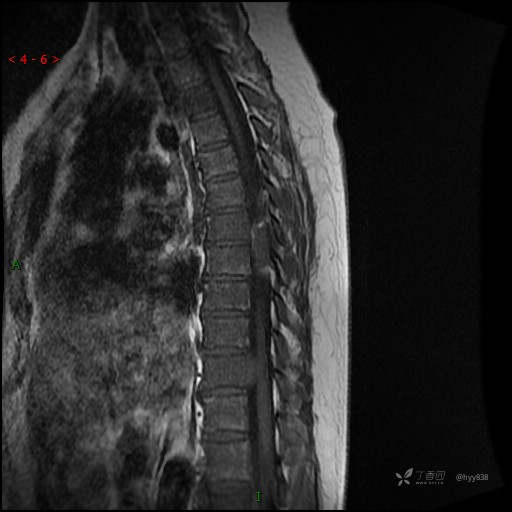

MRI SAG T2WI+T1WI